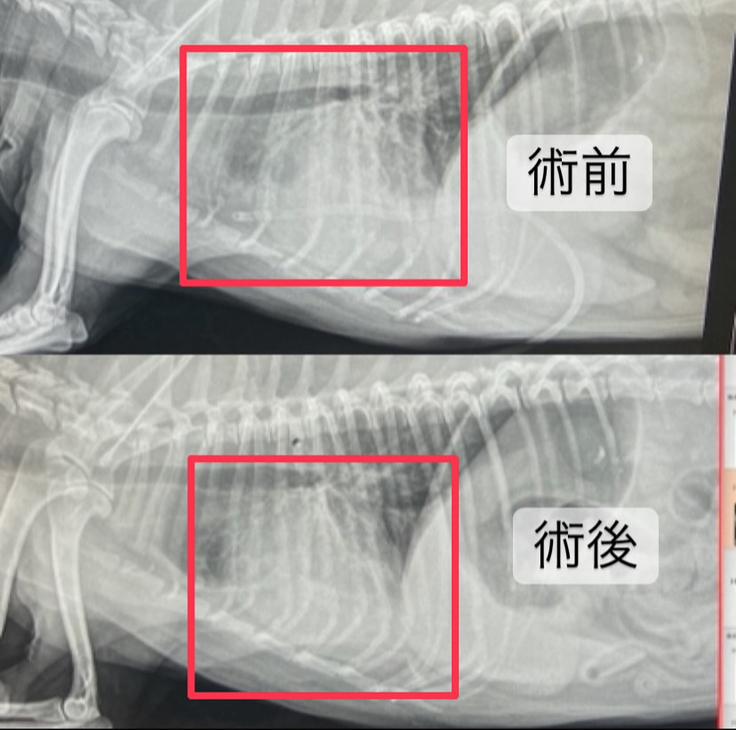

心臓の画像は術前に比べて心臓が小さくなっていて、白くなってしまっていたところも少し減っていました😭✨